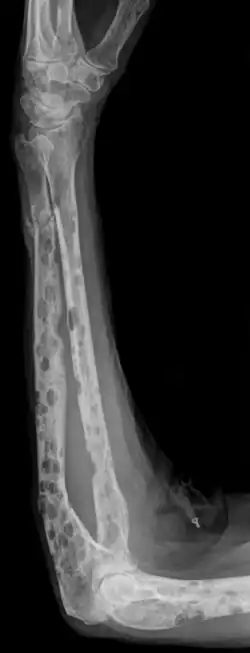

- Umotiverede knogleskader

- Røntgenundersøgelser kan i nogle tilfælde påvise forandringer i knoglerne.

- CT-scanning bruges ofte i de tilfælde, hvor der er mistanke om knogleforandringer, der ikke kan påvises med røntgen.